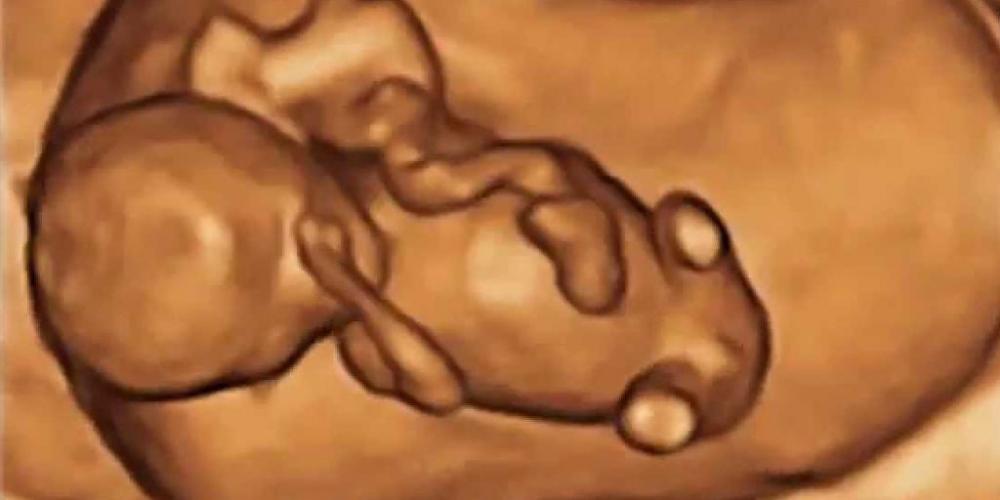

EN LA ARGENTINA YA MURIERON CASI 280.000 NIÑOS POR EL ABORTO LEGAL

La Dirección Nacional de Salud Sexual y Reproductiva del Ministerio de Salud de la Nación, a instancias del pedido de información de Notivida, informó que en 2023, el tercer año de vigencia de...